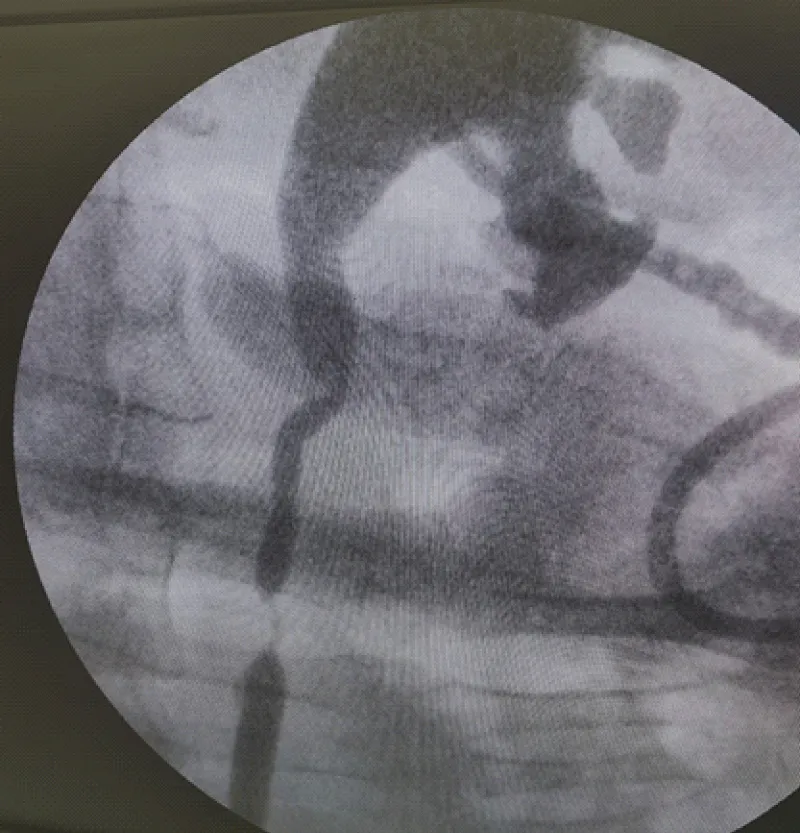

Contrast-enhanced CT demonstrated left-sided hydronephrosis/upper urinary tract dilatation without evidence of urolithiasis, raising suspicion for postoperative ureteral obstruction. Retrograde ureteral catheterization with attempted double-J stent placement was unsuccessful because the obstructed segment could not be traversed (Figure 1).

Figure 1: Retrograde attempt at ureteral stenting demonstrating inability to traverse the obstructed left ureteral segment.